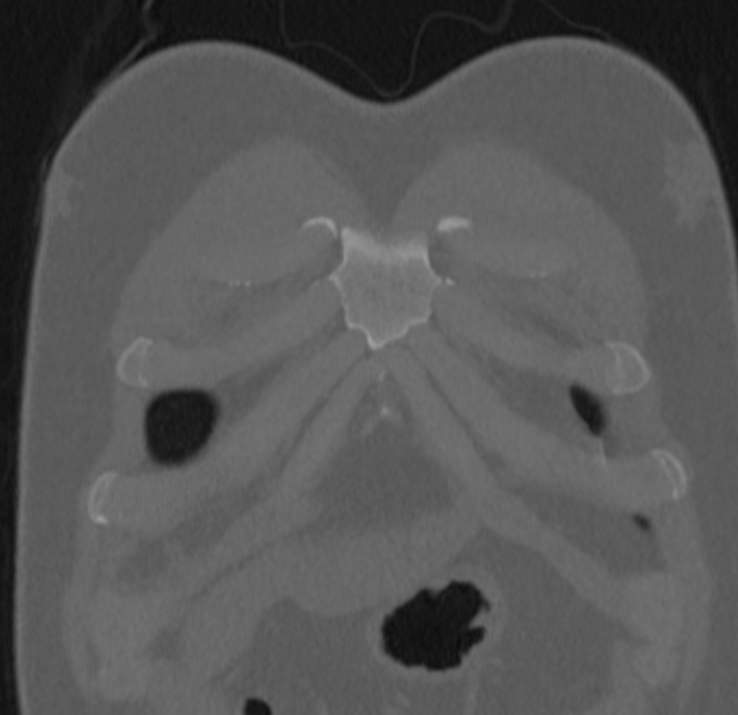

Все ребра задними концами соединяются с телами грудных позвонков. В норме у человека 12 пар ребер, из которых верхние 7 – это истинные ребра, спереди они имеют сочленения с грудиной. Следующие три пары соединяются хрящами с предыдущими ребрами и называются ложными. 11 и 12 пары ребер своими передними концами ни с чем не соединены и лежат свободно. Это свободные или колеблющиеся ребра.

Довольно часто встречаются различные вариации развития ребер. У некоторых людей могут отсутствовать нижние свободные ребра, либо наоборот быть лишняя 13 пара ребер. Также распространенным пороком развития является появление добавочных шейных ребер. Часто такие аномалии требуют хирургического удаления дополнительных ребер.

Компьютерная томография ребер позволяет обнаружить:

- дегенеративно-дистрофические изменения ребер, суставов

- воспалительные процессы как в ребрах, суставах, так и в прилегающих тканях и органах.

- травмы ребер, суставов

- осложнения после операции.

- новообразования

- метастазы

- планирование операций.